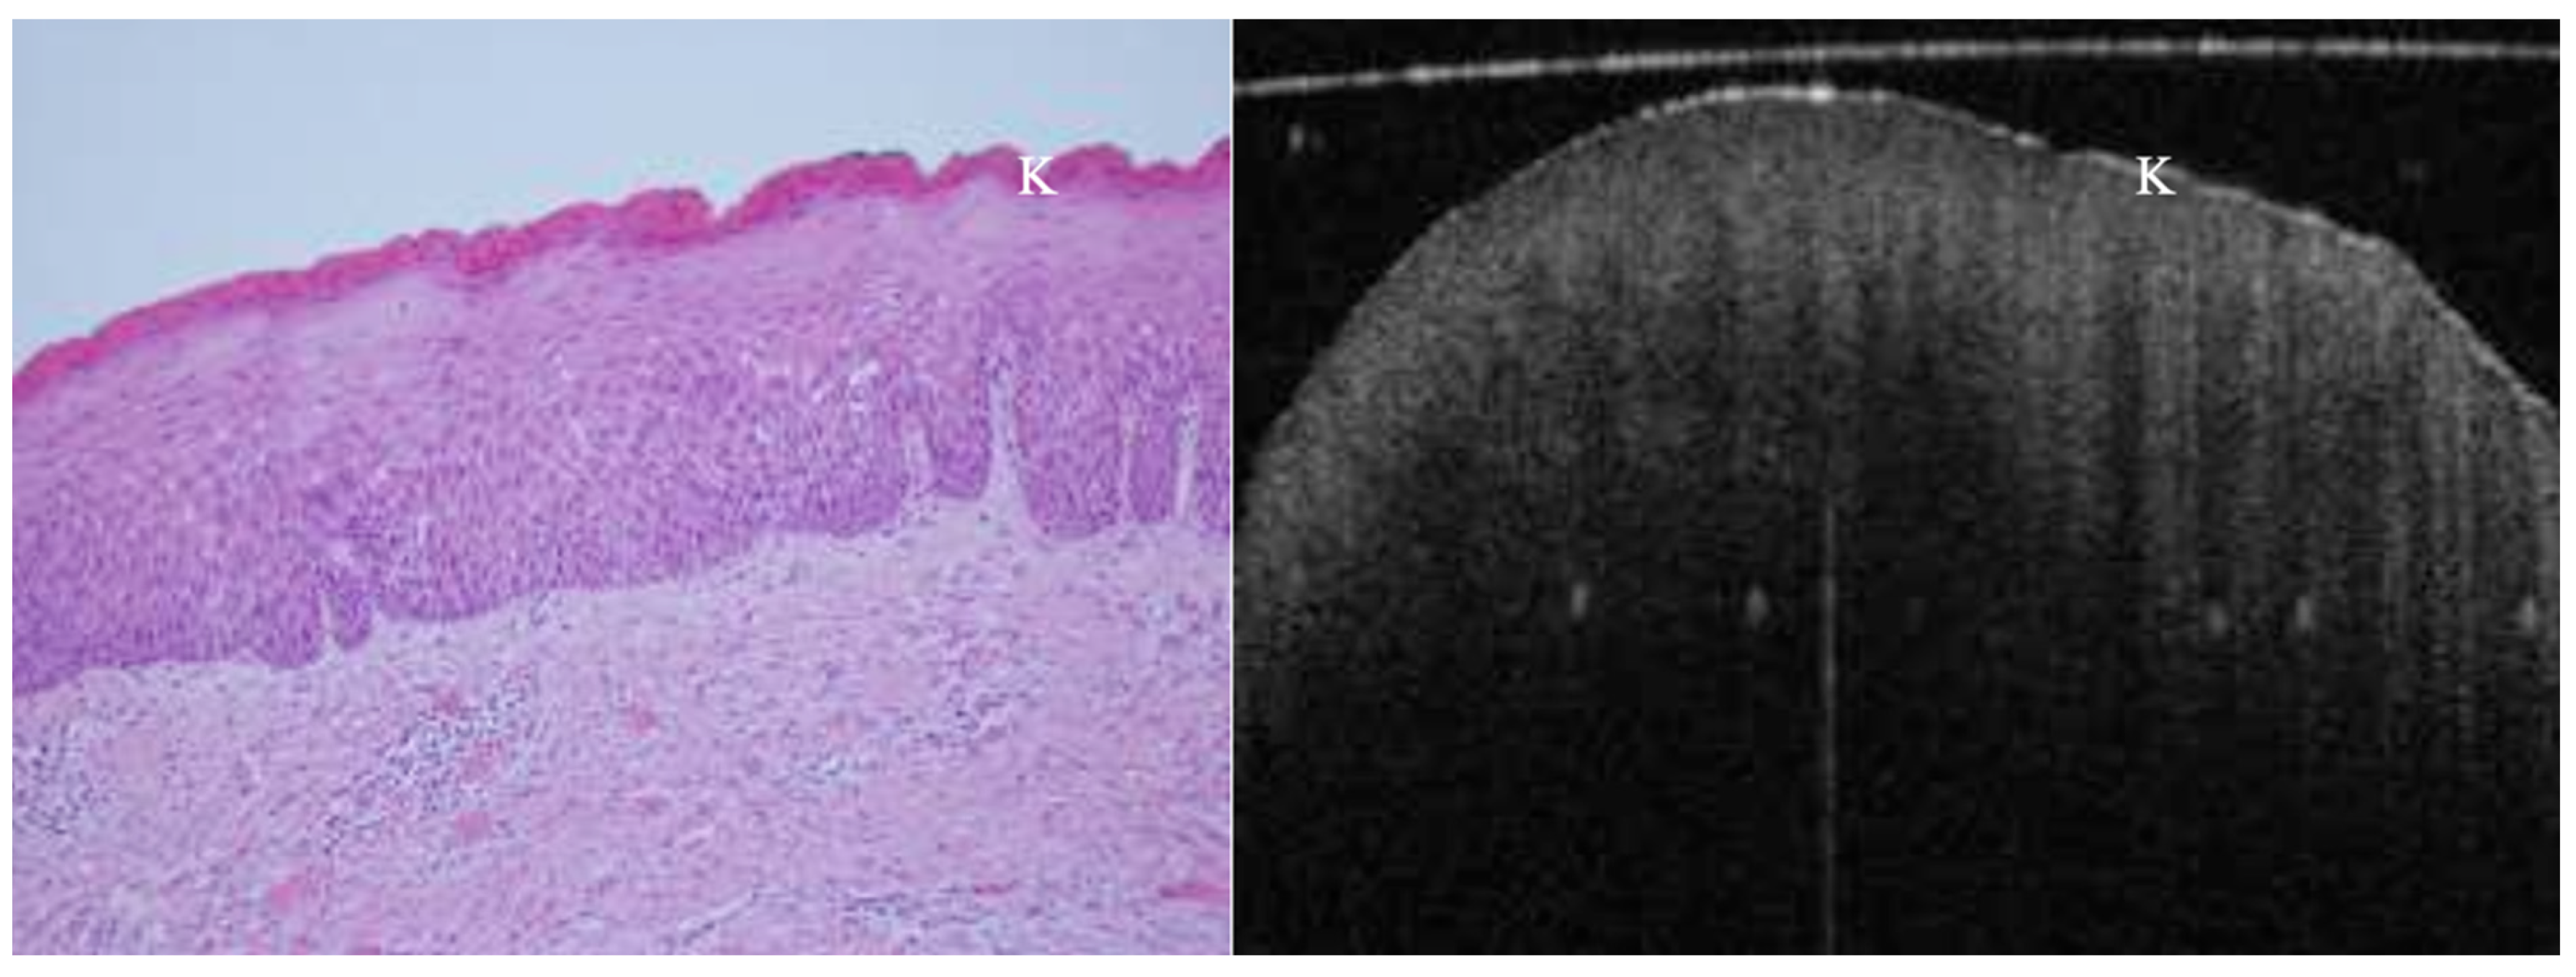

OCT performed well in discriminating dysplasia grades (Figure 1, Figure 2, Figure 3 and Figure 4). The AUC was 0.89 with an 88.0% sensitivity and 90.0% specificity for mild dysplasia. For moderate dysplasia, the highest accuracy was found: 85.0% sensitivity and 92.0% specificity yielded an AUC of 0.91. Severe dysplasia and CIS presented with lower values: the AUCs were 0.87 and 0.86, respectively (Table 4).

Figure 1. In vivo OCT and histopathology images of a white patch on the posterior lateral tongue reveal keratosis and mild to moderate epithelial dysplasia. K = keratosis.